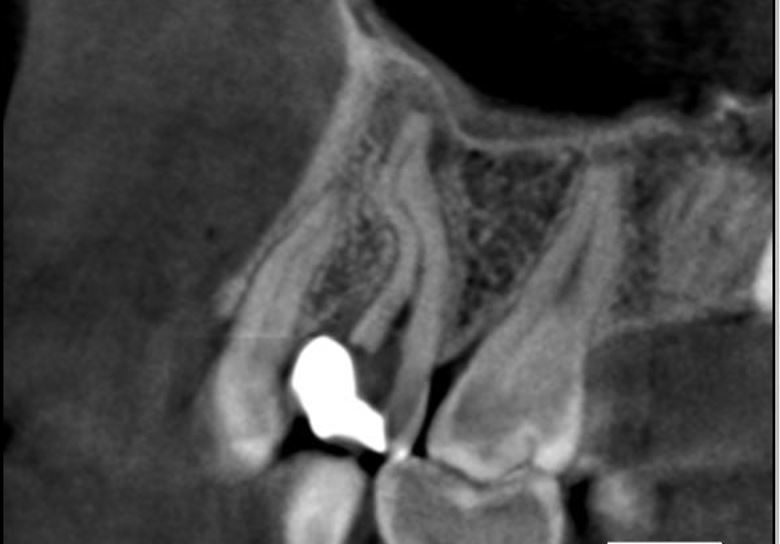

Clinical and radiographic examination revealed a short root filling and the presence of fractured instruments (image 1).